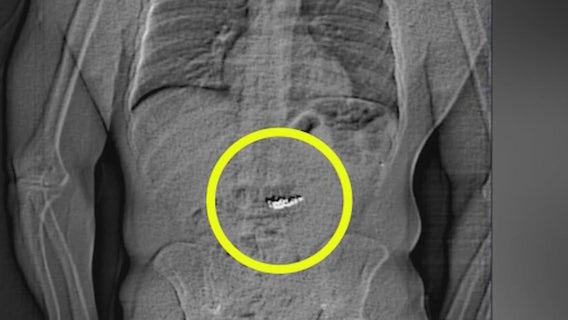

Texas man swallowed $700K in Tiffany earrings during alleged jewelry heist in Orlando, deputies say

A Texas man who claimed to represent an Orlando Magic player interested in purchasing nearly $1 million in jewelry from Tiffany & Co.